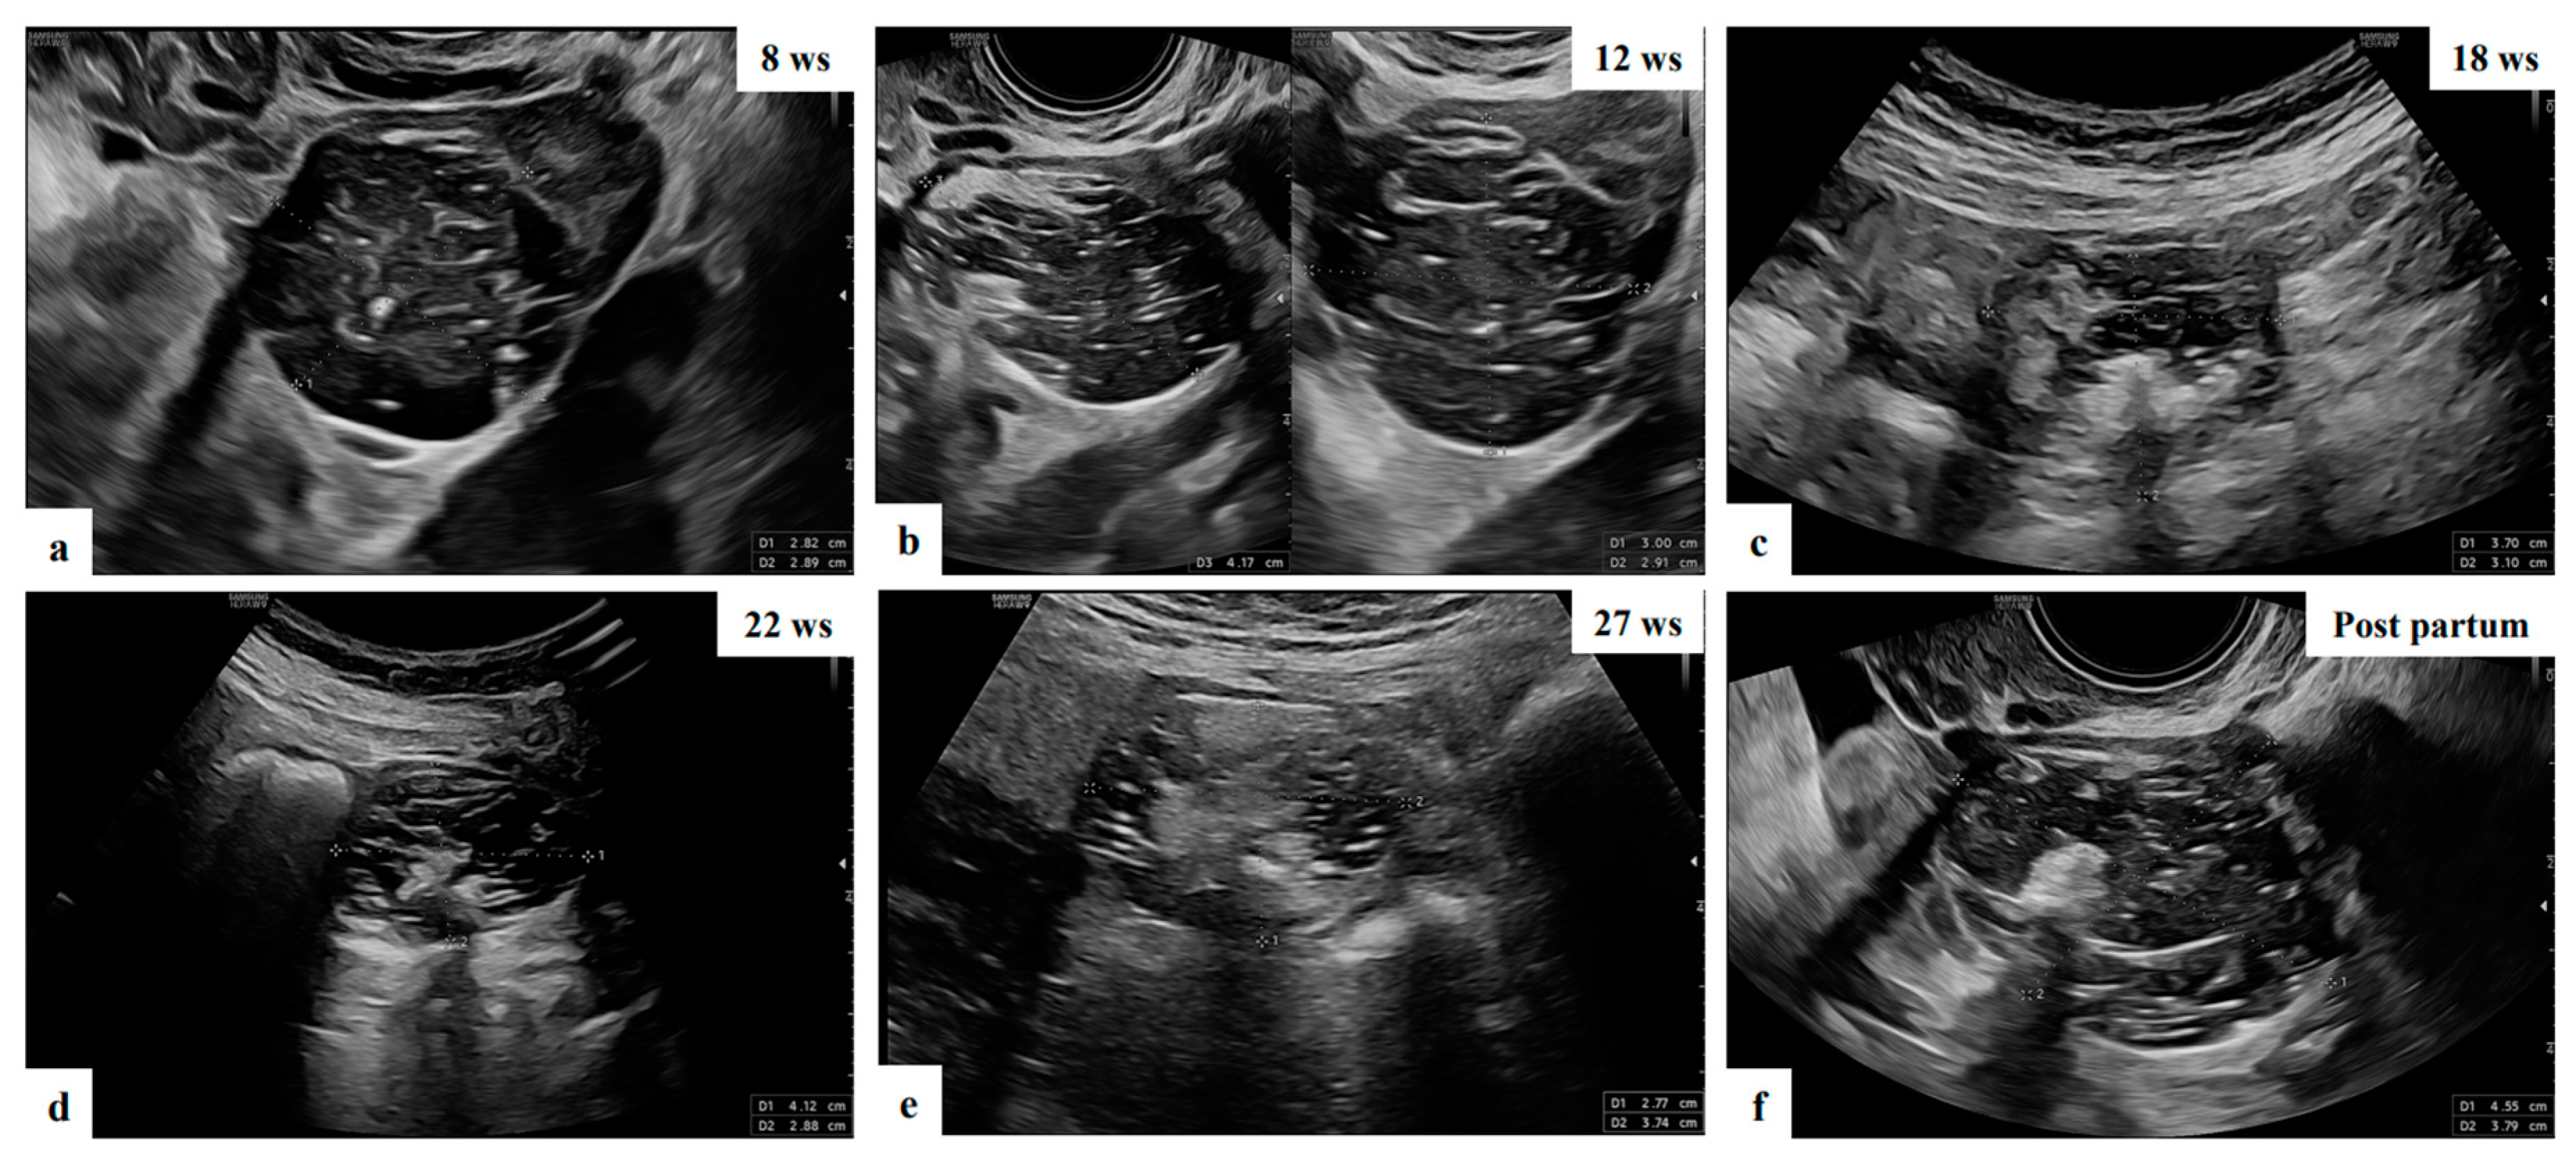

- Mascilini, F.; Moruzzi, C.; Giansiracusa, C.; Guastafierro, F.; Savelli, L.; De Meis, L.; Epstein, E.; Timor-Tritsch I., E.; Mailath-Pokorny, M.; Ercoli, A.; Exacoustos, C.; Benacerraf B., R.; Valentin, L.; Testa, A.C. Imaging in gynecological disease. 10: Clinical and ultrasound characteristics of decidualized endometriomas surgically removed during pregnancy. Ultrasound Obstet Gynecol 2014, 44, 354–360. [Google Scholar] [CrossRef]

- Pateman, K.; Moro, F.; Mavrelos, D.; Foo, X.; Hoo, W.L.; Jurkovic, D. Natural history of ovarian endometrioma in pregnancy. BMC Womens Health 2014, 14, 128. [Google Scholar] [CrossRef]